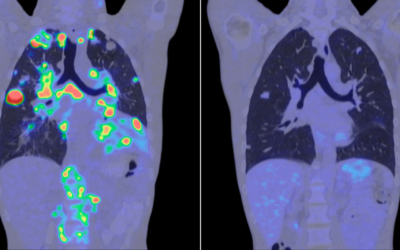

Investigación contra el càncer: 10 avances que traen esperanza

Investigación contra el càncer: 10 avances que traen esperanza Hablar de cáncer sigue siendo, para muchas personas, hablar de miedo, incertidumbre y desgaste. Pero sería injusto quedarse solo ahí. La investigación contra el cáncer está avanzando a gran velocidad y,...

La inteligencia artificial abre una nueva etapa en la investigación contra el cáncer

La inteligencia artificial abre una nueva etapa en la investigación contra el cáncer La inteligencia artificial ha dejado de ser una promesa futura para convertirse en una herramienta real dentro del ámbito sanitario. En los últimos meses, distintos estudios han...